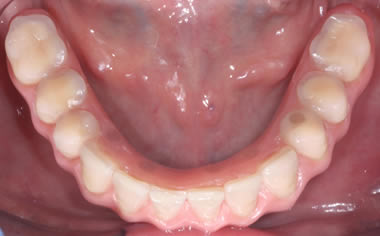

Full arches of teeth replaced by dental implants

Case One (5 images)

Full set of lower teeth fixed onto five dental implants.